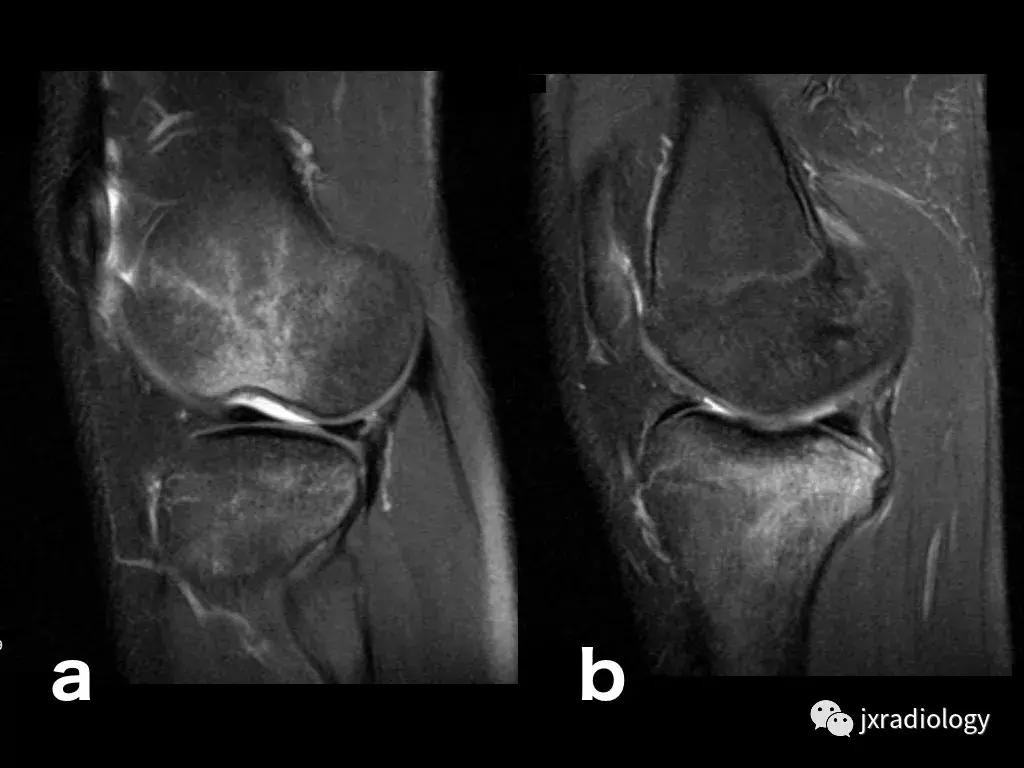

图4:SIF(软骨下不全性骨折):在过去,每当在股骨内侧髁上观察到这种软骨下病变时,它就被标记为膝关节自发性骨坏死(SONK)。现在它被认为是一个不全性骨折。这些不全性骨折通常发生在股骨内侧髁和股骨头,并存在于老年人中(它们与骨质疏松症和生物力学改变相关,如在不稳定的半月板损伤中。与其他应力性骨折类似,低信号的骨折线在水敏性序列(a,b:冠状和矢状PDWI-FS)上被高信号的骨髓水肿包围。

图5:长期的SIF(软骨下不全性骨折)伴股骨外侧髁软骨下塌陷、大面积水肿(不如上图中显示的内侧髁位置常见)。

图6:内侧胫骨平台上不常见的SIF(软骨下不全性骨折)(a,b:矢状和冠状PDWI-FS)。